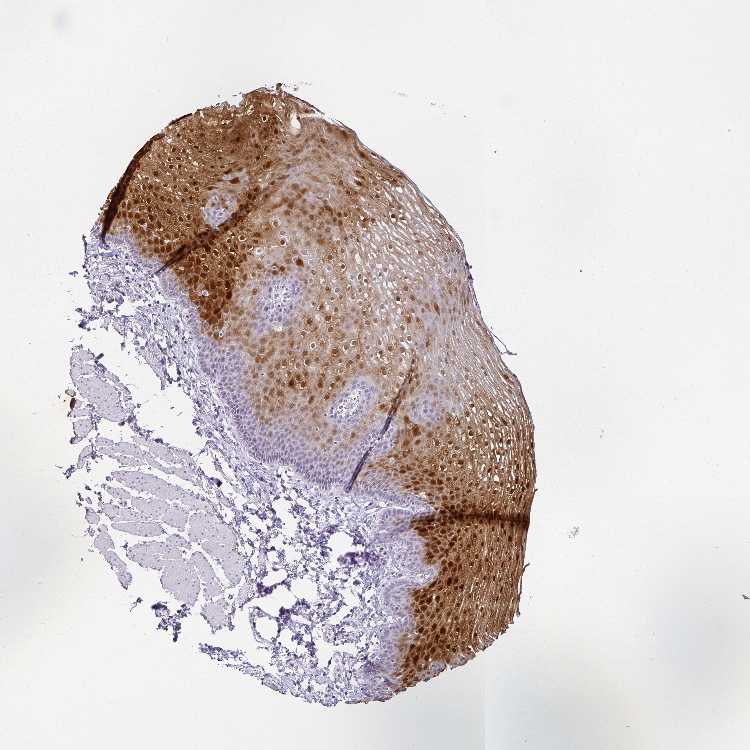

ESOPHAGUS - Antibody stainingi

Antibody staining in the annotated cell types in the current human tissue is reported as not detected, low, medium, or high, based on conventional immunohistochemistry profiling in selected tissues. This score is based on the combination of the staining intensity and fraction of stained cells.

Each image is clickable and will lead to virtual microscopy that enables deeper exploration of all samples and also displays staining intensity scores, fraction scores and subcellular localization as well as patient and tissue information for each sample.

Antibody HPA048341Antibody HPA049988Antibody HPA055992Antibody CAB018772Antibody CAB036007

Squamous epithelial cells MediumMediumMediumHighHigh